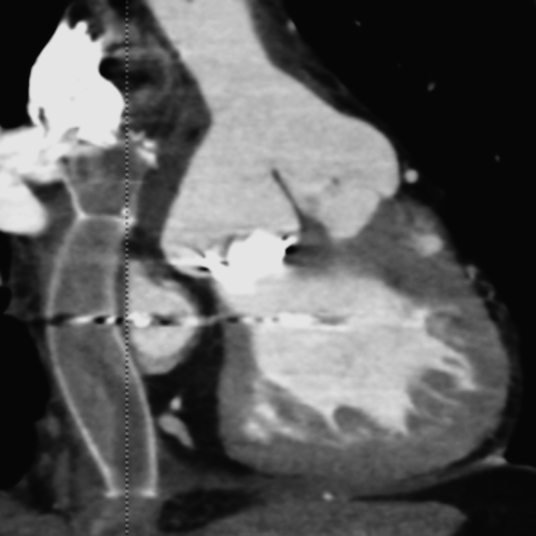

造影CT検査

導管内に粗大な石灰化あり,内腔の狭小化を認めた(Fig. 2).

Pediatric Cardiology and Cardiac Surgery 36(1): 84-89 (2020)

Fig. 2 Preoperative computed tomography showing papillary calcification in the conduit in patient 1